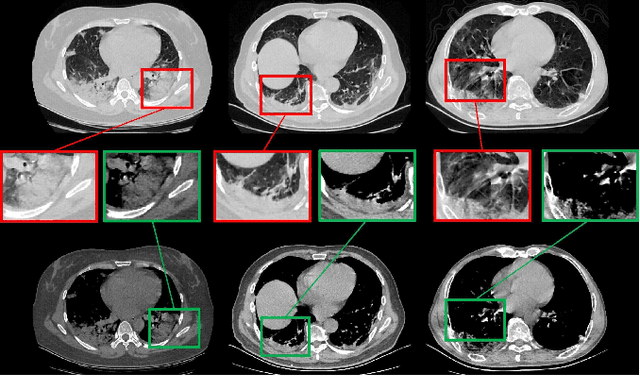

Abstract:A novel coronavirus disease 2019 (COVID-19) was detected and has spread rapidly across various countries around the world since the end of the year 2019, Computed Tomography (CT) images have been used as a crucial alternative to the time-consuming RT-PCR test. However, pure manual segmentation of CT images faces a serious challenge with the increase of suspected cases, resulting in urgent requirements for accurate and automatic segmentation of COVID-19 infections. Unfortunately, since the imaging characteristics of the COVID-19 infection are diverse and similar to the backgrounds, existing medical image segmentation methods cannot achieve satisfactory performance. In this work, we try to establish a new deep convolutional neural network tailored for segmenting the chest CT images with COVID-19 infections. We firstly maintain a large and new chest CT image dataset consisting of 165,667 annotated chest CT images from 861 patients with confirmed COVID-19. Inspired by the observation that the boundary of the infected lung can be enhanced by adjusting the global intensity, in the proposed deep CNN, we introduce a feature variation block which adaptively adjusts the global properties of the features for segmenting COVID-19 infection. The proposed FV block can enhance the capability of feature representation effectively and adaptively for diverse cases. We fuse features at different scales by proposing Progressive Atrous Spatial Pyramid Pooling to handle the sophisticated infection areas with diverse appearance and shapes. We conducted experiments on the data collected in China and Germany and show that the proposed deep CNN can produce impressive performance effectively.